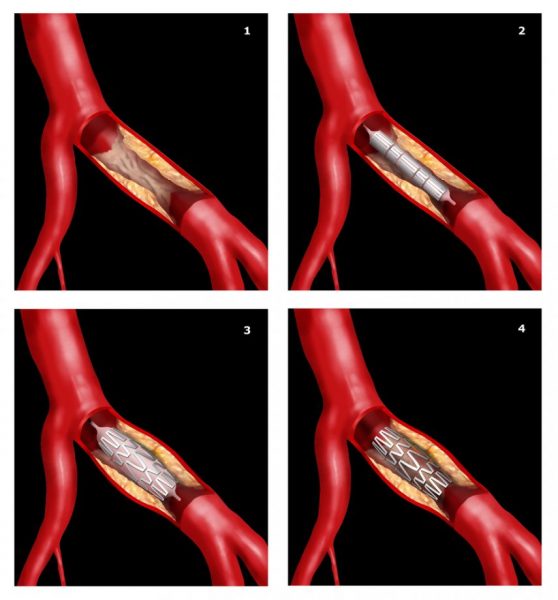

Αγγειοπλαστική με stent

Κατά την αγγειοπλαστική με stent, με ειδικούς καθετήρες φτάνουμε στο σημείο της απόφραξης μιας αρτηρίας και με ειδικούς ενδαγγειακούς νάρθηκες (stent) ή διαστολή με μπαλόνι ξανανοίγουμε την αρτηρία που έχει αποφραχθεί. Η αγγειοπλαστική μπορεί να γίνει από την κοιλιακή αορτή, τις λαγόνιες έως τις αρτηρίες των κάτω άκρων.